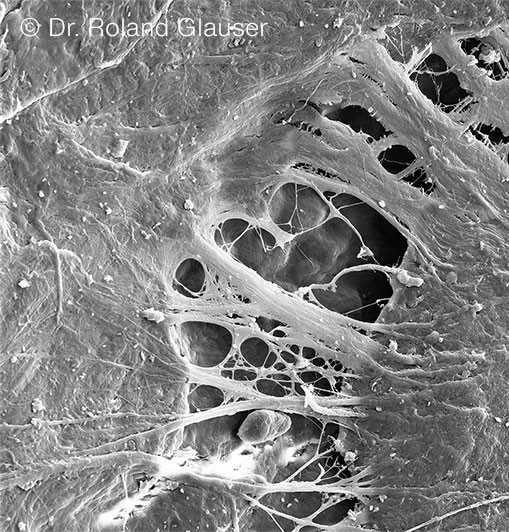

Voraussetzung für das Entstehen einer mukosalen Schutzbarriere ist das Verwachsen von Weichgewebe mit dem Halsbereich von Symbionic Teeth. Dieser Vorgang konnte bei Symbionic Teeth der Marke Patent™ erstmals überhaupt für eine Zahnersatzlösung nachgewiesen werden (Abb. 1).3-5

| Abb. 1: Rasterelektronenmikroskopische Aufnahme zeigt das Verwachsen von Weichgewebe mit Patent™ Symbionic Teeth (© Dr. Roland Glauser). | Abb. 2: Histologischer Querschnitt zeigt den Verbund zwischen Saumepithel (JE) und Patent™ Oberfläche, welcher die Migration von Plaque und Zahnstein (CAC) in die Gewebe verhindert (© Dr. Peter Schüpbach). |